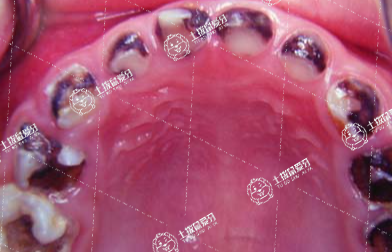

隨著大家思想觀念的進一步開放,在臨床上,當牙友們?nèi)绻醒例X問題的話,尤其是齲齒壞掉后需要牙友們及時做補牙處理,補牙需要多少錢補一顆?這或許是牙友們比較在意的事情,接下來,我們一起來了解一下。

補牙收費價格一般在200元到800元之間。補牙收費一般與補牙材料,自身牙齒的受損程度有關(guān)。

常見的補牙材料主要有樹脂、玻璃離子等,牙齒受損程度一般分為牙齒損壞,蛀牙等情況。若使用樹脂原材料,且牙齒只是損壞一點,那么進行簡單的修補就可以了,價錢也比較親民,一般在200元到300元之間。若牙齒損害嚴重,有疼痛感需要進行徹底根治和修復(fù)補牙,費用最低也要三四百元。

補牙需要多少錢補一顆

若使用玻璃離子原材料,且牙齒損傷不大,由于玻璃離子對牙齒刺激性比較小,價錢一般在400元到500元之間。若牙齒有蛀牙、牙冠齲壞等情況,那不僅要進行修復(fù)治療,還要進行拔牙,費用比較昂貴,一般在500元到800元之間。